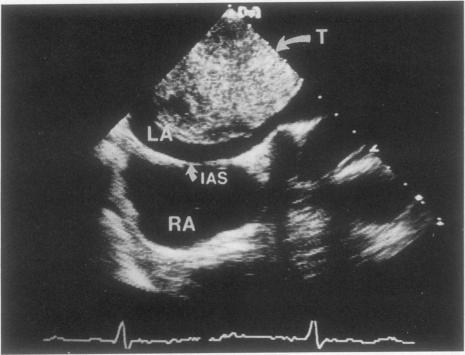

Transesophageal echocardiography and 2-dimensional transthoracic echocardiography have proved to be extremely valuable in the diagnosis of cardiac masses. In this report, we review the echocardiographic findings, clinical history, and histopathologic findings in 21 patients with intracardiac masses who underwent transthoracic echocardiography, transesophageal echocardiography, or both, at our institution. Of these patients, 14 had benign masses and 7 had malignant tumors. The potential role of transesophageal echocardiography in the diagnosis and treatment of patients with intracardiac masses is discussed. We believe that transesophageal echocardiography offers the cardiologist and cardiovascular surgeon the capability of more accurate preoperative and intraoperative assessment of cardiac masses.

经食管超声心动图和二维经胸超声心动图已被证明在心脏肿物的诊断中极具价值。在本报告中,我们回顾了在我院接受经胸超声心动图、经食管超声心动图或两者检查的21例心内肿物患者的超声心动图表现、临床病史及组织病理学发现。这些患者中,14例为良性肿物,7例为恶性肿瘤。讨论了经食管超声心动图在心脏肿物患者诊断和治疗中的潜在作用。我们认为经食管超声心动图为心脏病专家和心血管外科医生提供了更准确地进行心脏肿物术前和术中评估的能力。